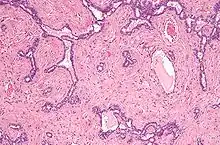

Le rete testis est un réseau de canaux des testicules issus des tubes séminifères droits dans le mediastinum testis.

Les canaux du rete testis s'écoulent dans les canaux efférents, qui passent dans la tête de l'épididyme. À ce niveau, le rete testis ne contient que des cellules de Sertoli, puisque tous les spermatozoïdes se trouvent dans la lumière des tubes séminifères.